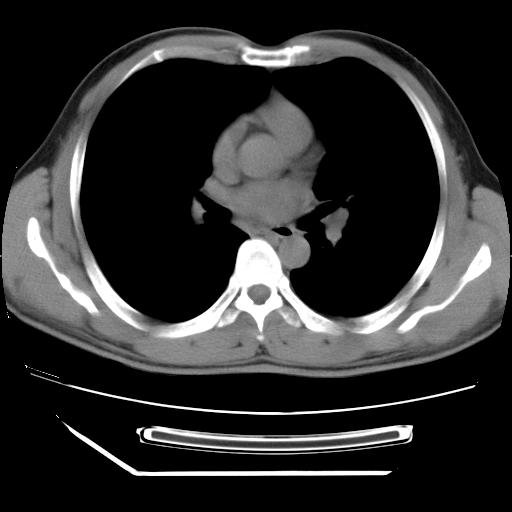

男,38岁,于2009年8月9日晚突发左侧胸痛,今x线提示左下肺阴影,为了明显确诊断,行ct检查,

纵膈窗

左肺舌叶病变。主体病灶呈类圆形中心密度低,成液化趋势周边班片影分布

考虑肺脓肿

虽然实验室检查支持炎性病变,且病变内有坏死改变(中央呈大片状低密度影),但仍不能掉以轻心,鳞癌也可以有这种影像改变。